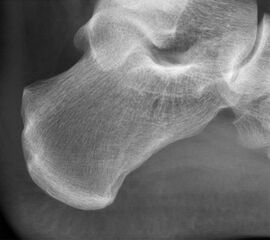

Abbildung 10, Video 5

Das OP-Ergebnis wird mit dem Bildwandler dokumentiert. Hierbei ist es wichtig, auch mediale und laterale Schrägaufnahmen anzufertigen, um keine weit posteromedial oder -lateral gelegenen Exostosenreste zu übersehen (Calcaneus seitlich, sowie 45° Innen- und Außenrotation). Ergänzend zu Röntgenaufnahme sollte der mediale und laterale Calcaneus abgetastet werden, um das Risiko einer belassenen Knochenkante möglichst gering zu halten. Der Hautverschluss erfolgt in Einzelknopftechnik, eine Ruhigstellung ist nicht erforderlich.

Abbildung 11-12

Prä- und postoperatives Röntgenbild.